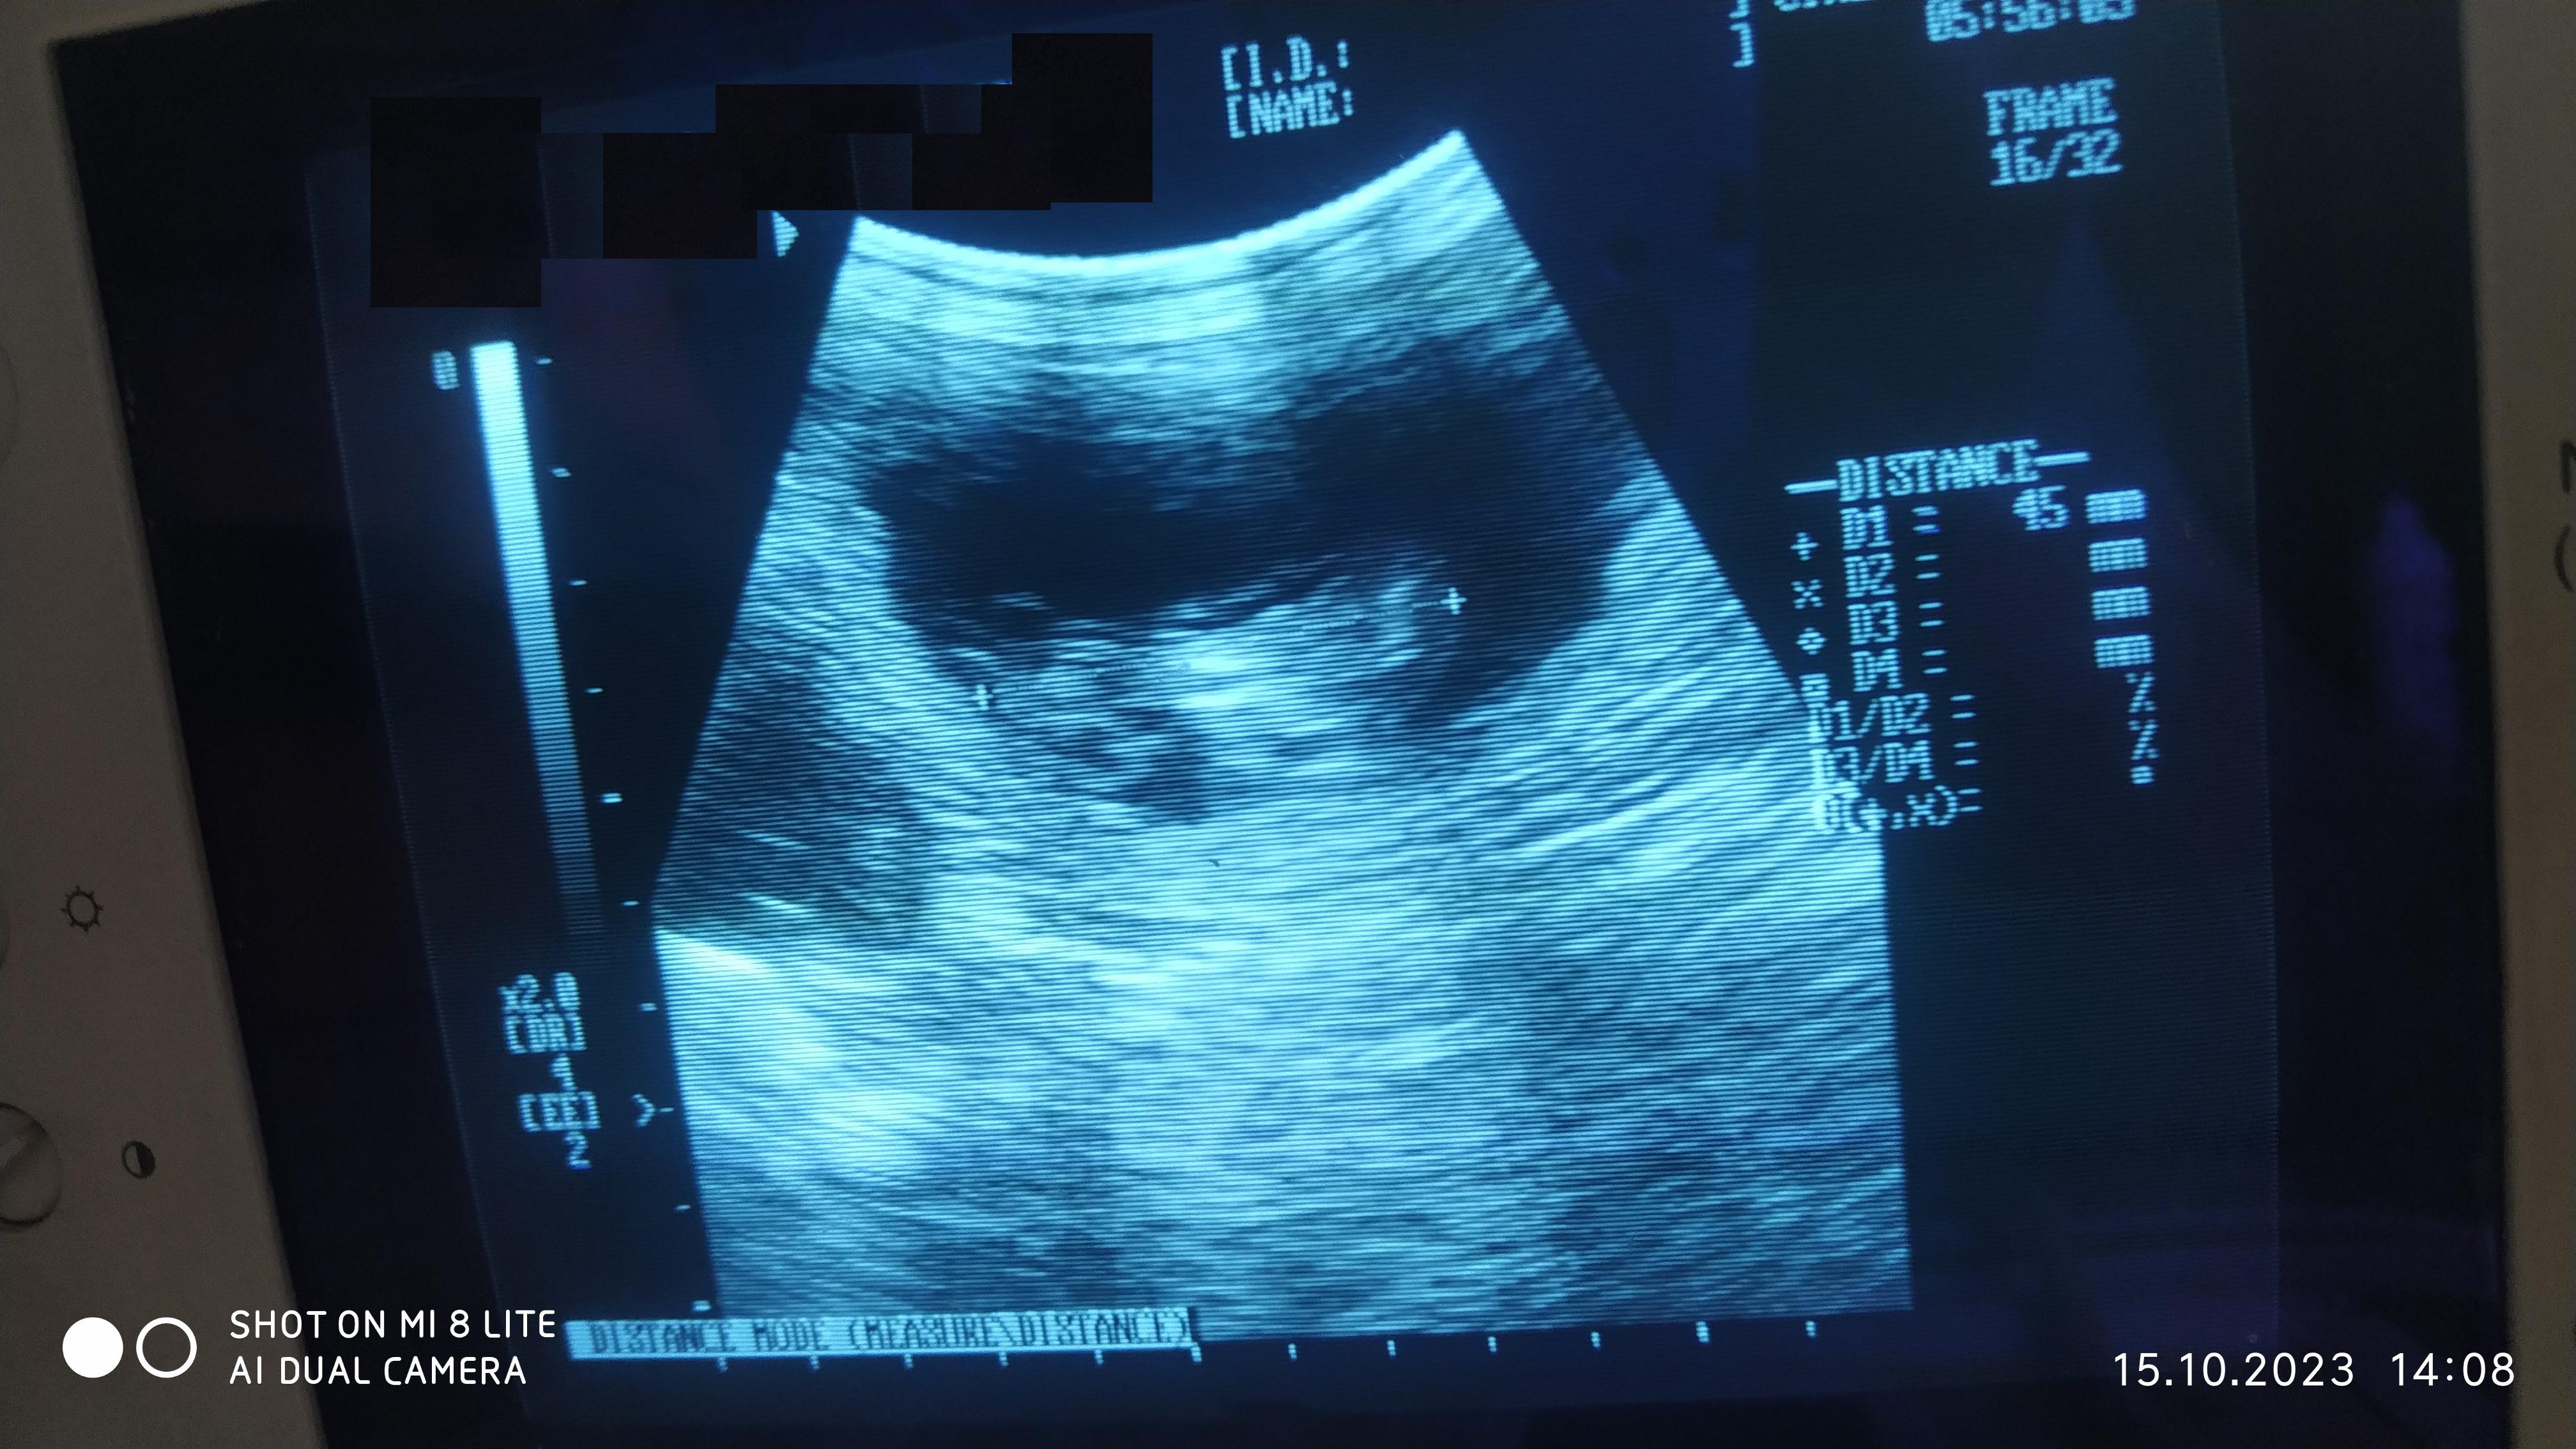

W oczekiwaniu na narodziny, przeprowadziliśmy badanie USG suki JAVY, która była kryta kilka tygodni po kryciu Rimy. Poniżej wynik badania.

Około 35 – 36 dzień ciąży.

Długość szczenięcia, jak widoczna na pomiarze 45 mm.

Około 35 – 36 dzień ciąży.